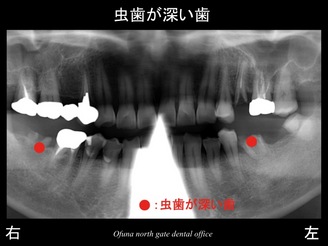

それでは初診時のレントゲンから見てみましょう。

右下の奥歯と左下の奥歯の被せ物が取れてしまったため、

『奥歯で物が噛めない!』との問題から当医院を受診されました。

診査をすると被せ物が取れた歯は、虫歯が非常に深い状態でした。

上顎の左側の奥歯も被せ物が取れている状態でした。

これらの歯は神経がない歯です。

以下の青丸:●が神経がない歯です。